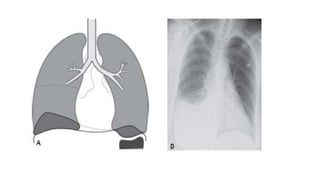

• X ray shows

• Cervicothoracic Sign

• Widening of the paravertebral stripes